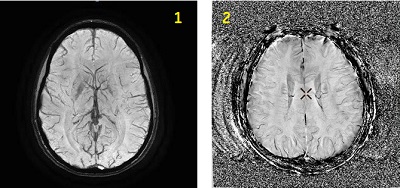

SWAN scan

Use SWAN to acquire 3D, high-resolution, susceptibility enhanced (heavy T2*-weighted) multi -echo gradient echo head scans that produce echo-combined images. It reduces geometric distortion and the high bandwidth (31.25 kHz or higher) helps to avoid chemical shift artifacts. Both paramagnetic and diamagnetic tissues show similar behavior on magnitude images generated from the SWAN application. SWAN phase images provide enhanced visualization of local magnetic field changes in the presence of paramagnetic and diamagnetic substances.

| 1 | SWAN reformatted image |

| 2 | SWAN Phase reformatted image |

Consider this information when modifying SWAN scan parameters. For specific scan parameter values, select a protocol from your GE or Site library.